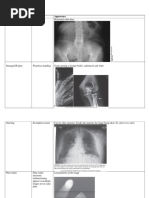

DIGITAL ARTIFACT TYPE:

Dirt on Light

(optics, mirrors, lenses, and light guides)

CAUSE(S):

* Imaging plate handling

* Plate in and out of cassette thorough CR reader

APPEARANCE:

Horizontal white lines on image